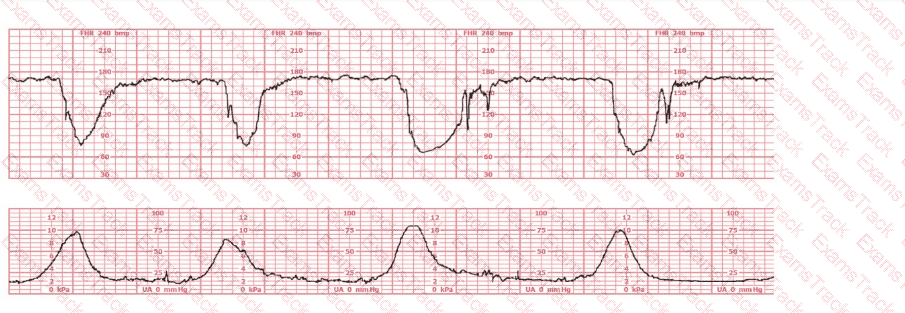

The fetal heart rate baseline is approximately 150 bpm, which is within the normal range of 110–160 bpm.

The tracing shows minimal variability (approximately 1–4 bpm amplitude). Minimal variability for a sustained period is categorized as a Category II pattern under NCC/NICHD classification.

No accelerations are present during the 20-minute representative segment.

There are no recurrent variable, no recurrent late, and no prolonged decelerations.

The tracing shows very frequent contractions—approximately every 1½ to 2 minutes, which meets the NCC definition of tachysystole when averaged over 10 minutes (more than 5 contractions in 10 minutes).